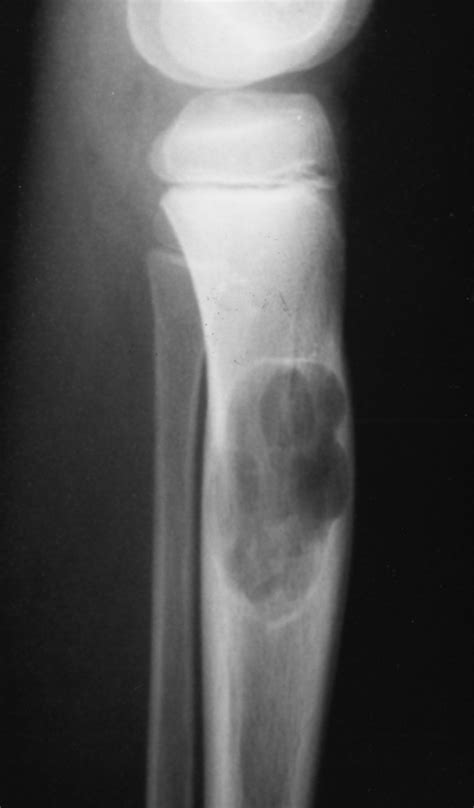

When a patient presents with persistent, unexplained bone pain, especially in children, adolescents, or young adults, medical professionals often prioritize imaging to rule out malignancies. Among the various diagnostic tools available, the Osteosarcoma X Ray is frequently the first line of investigation. Osteosarcoma is the most common primary bone cancer in children and adolescents, and while X-rays are not definitive for diagnosis on their own, they provide crucial radiographic features that help radiologists and orthopedic oncologists identify suspicious lesions. Early detection is paramount for improving patient outcomes, making the interpretation of these initial radiographs a vital component of the diagnostic journey.

The primary goal of the initial X-ray is to assess for "aggressive" features that distinguish a potentially malignant tumor from a benign one. Radiologists look for specific patterns of bone destruction and the body’s reaction to the lesion. While these imaging findings can be highly suggestive, they must always be correlated with the patient's clinical history, physical examination, and subsequent pathological analysis.

• Sunburst Pattern: Radiating spicules of bone formation that extend outward from the tumor into the soft tissue.

• Codman’s Triangle: A triangular formation of new bone that occurs when the tumor grows faster than the periosteum (the outer covering of the bone) can form new bone, resulting in an elevation of the periosteum.

Interpreting an Osteosarcoma X Ray requires a nuanced eye. Osteosarcoma is heterogeneous, meaning it can present in several different ways depending on its subtype and location. The appearance of the lesion often depends on whether it is predominantly osteoblastic (bone-forming) or osteolytic (bone-destroying).